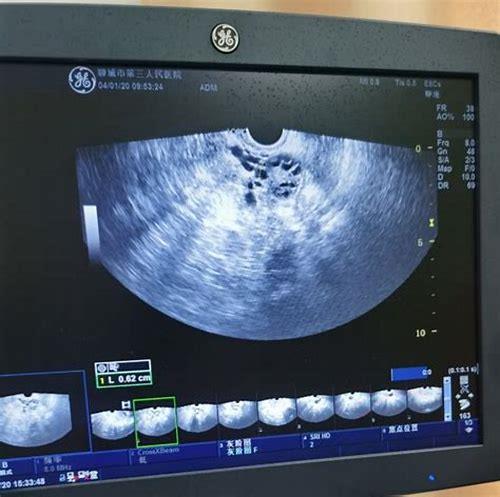

备孕卵泡监测的方法包括超声波检查、基础体温测定、宫颈黏液观察等,超声波检查是最常用的方法,通过高频超声波扫描,可以清晰地观察到卵泡的生长和发育情况,基础体温测定则是通过测量女性在睡眠中的体温变化,了解排卵周期,宫颈黏液观察则是通过观察宫颈黏液的变化,判断排卵时间。

女性的卵巢每月会释放一枚成熟卵子,这一过程称为排卵,然而并非所有卵泡都能顺利长大并排出优质卵子——部分女性可能存在多囊卵巢综合征、激素失衡或黄体功能不足等问题,导致卵泡生长异常(如过小、停滞或过早萎缩),通过B超下的动态观察,医生可以清晰看到卵泡的大小、数量、形态变化以及子宫内膜厚度,从而判断排卵是否正常,是否存在优势卵泡主导发育的情况,这种可视化追踪不仅能帮助识别潜在生育障碍,还能为自然受孕或辅助生殖技术提供精准指导。

目前临床最常用的方法是经阴道彩色多普勒超声检查(TVS),其优势在于分辨率高且无需憋尿,可从月经周期第8-10天开始首次检测,建议每2天复查一次,当发现最大卵泡直径达18mm以上时改为每日监测,直至确认排卵发生,整个过程中需要注意三个核心指标:一是主卵泡的生长速率(理想情况下每天增长约2mm);二是子宫内膜同步增厚情况(适宜着床的厚度通常在8-12mm之间);三是是否出现“消失征”——即原本可见的优势卵泡突然不见,提示已成功排卵。

另一个普遍存在的认知偏差是将“大卵泡”等同于“高质量卵子”,实际上,过大的卵泡可能伴随空泡化风险,反而降低受孕概率,理想的成熟卵泡应具备均匀透亮的外观、清晰的边界和适中的张力感,这些细节都需要经验丰富的医师来评判。